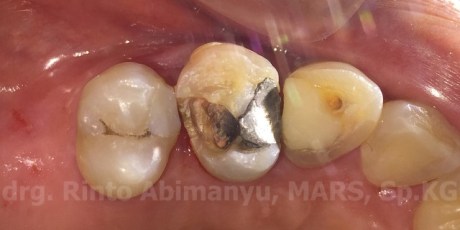

Seluruh restorasi lama dibongkar dan jaringan karies sekunder dihilangkan menggunakan bur carbide low speed, email yang tipis dan tidak terdukung cukup dentin juga dihilangkan..

Setelah pembersihan kavitas

Dilanjutkan dengan pembuatan artificial wall atau pre endodontic build up, pada kasus ini tidak dilakukan cauter gingiva karena tepi dari kavitas masih berada di atas gingiva dan masih memungkinkan untuk dipasang matriks dan mendapatkan kerapatan yang baik..

Matriks yang dipakai adalah greater curve matriks dan bahan restorasi menggunakan komposit..

Selesai pembuatan artificial wall